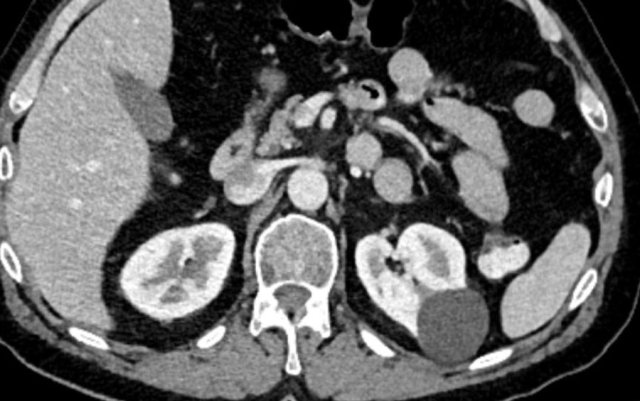

case 1

CT of a solid lesion with smaller cystic/necrotic components.

As more than 25% of the mass is composed of solid tissue this likely represents a necrotic mass in stead of a cystic lesion.

Bosniak criteria should not be used.